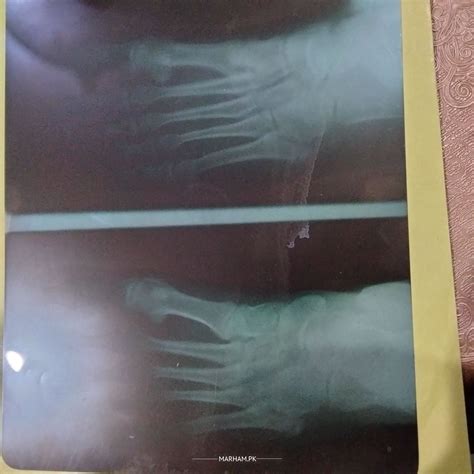

Stress Fracture Foot Healing Timeline